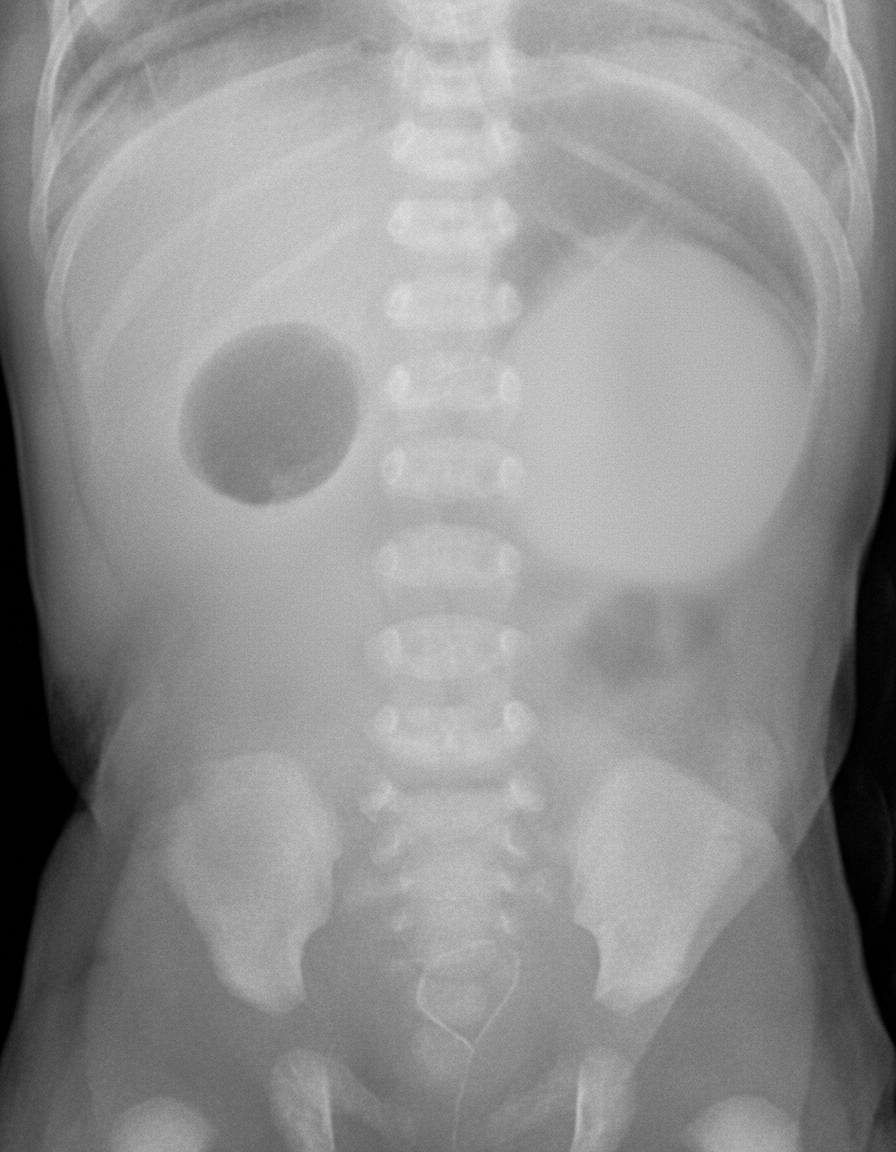

A 45-year-old gravida 1, para 0 woman is brought to the hospital in labor at 39 weeks gestation. After 4 hours, she gives birth to a healthy appearing baby boy with APGAR scores of 7 at 1 minute and 9 at 5 minutes. She had limited prenatal screening but did have an ultrasound at 35 weeks that showed polyhydramnios. The next day, the neonate vomits greenish-yellow fluid after breastfeeding. This occurs 2 more times that day after feeding and several times between feedings. The next day, the neonate appears weak with difficulty latching to the breast and is dehydrated. The physician on duty is concerned and orders blood work, IV fluids, and the abdominal X-ray shown below. Which of the following disorders is most associated with the newborn’s condition?